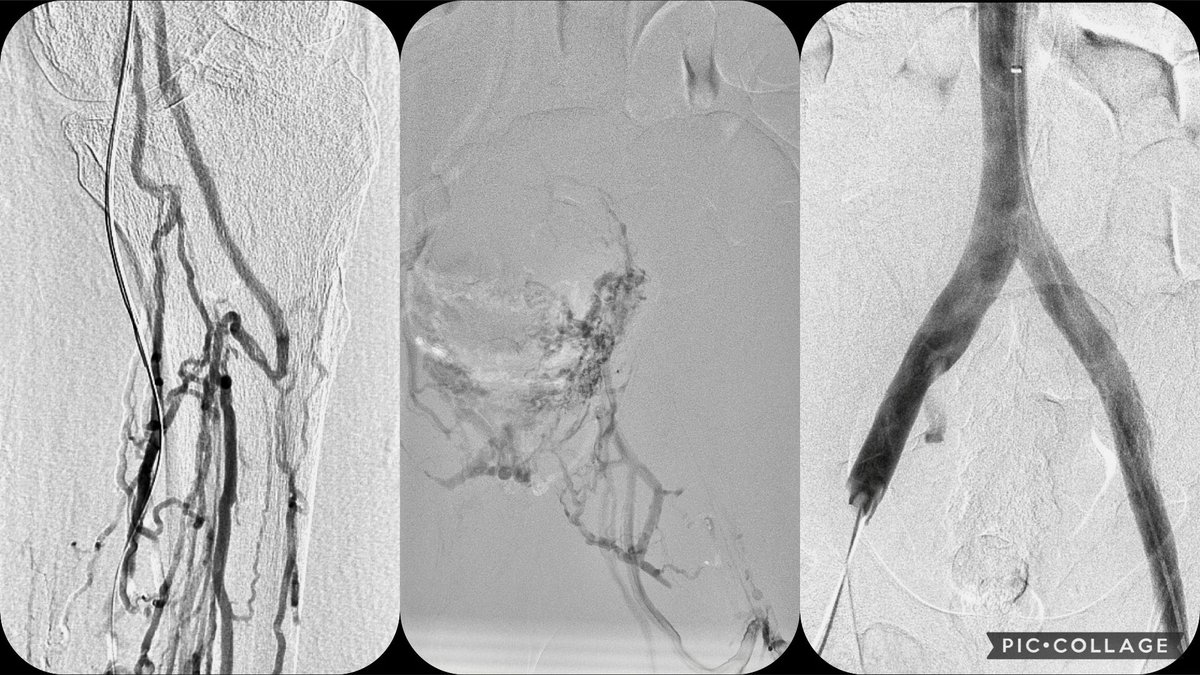

Covered stent assisted coiling of internal iliac artery for uretero-arterial fistula at the bifurcation of iliacs. Telescoping funnel technique for stent graft in the iliacs to prevent endoleak. #VIR #EndoVascular #EmergenciesInAngiosuite Society of Interventional Radiology SIR RFS SIR ECS